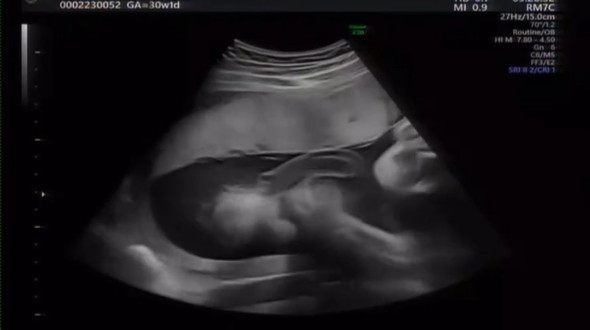

「えっと、、これよりホラーなエコーありますか、、。」

画像提供:KITO(@ki_to1018)さん